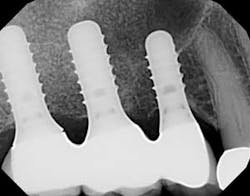

This patient had with a noncontributory medical history. Implants were placed in the upper right maxillary quadrant in 2006, and the patient came in for six-month recare visits. Ideally, he would have regularly alternated between the periodontist and the general dentist for care, but the patient elected only to be treated for maintenance intervals at the general dentist’s office. Significant bleeding and pocketing around the implants was noted eight years later in 2014, but there was no radiographic evidence of bone loss. (figures 1 and 1a).